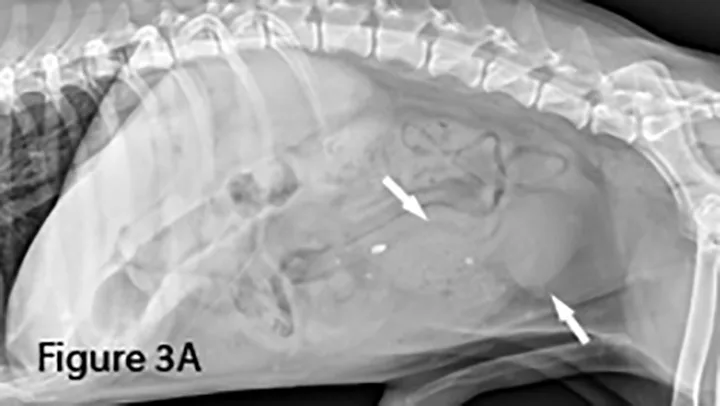

A foreign body (ie, rock) is identifiable in this canine small intestine. The markedly dilated segment of jejunum (arrows) leading up to the foreign body (~4× the height of L5) is significant.